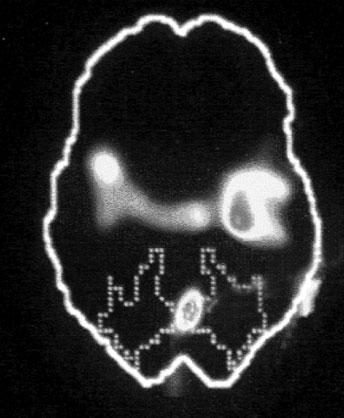

А. Правая лимбическая область

Б. Зрительная кора

В. Зона Брока

Изображение мозга в процессе переживания травмы. Светлые пятна в лимбической коре (А) и зрительной коре (Б) соответствуют повышенной активности мозга в этих участках. На снимке (В) видна значительно пониженная активность речевого центра мозга.

Когда через эту процедуру прошли все восемь участников, Скотт Рауч вместе со своими математиками и статистиками взялся за создание составного снимка, по которому можно было бы наглядно сравнить активность мозга в нейтральном состоянии и в момент появления неприятных воспоминаний. Несколько недель спустя он отправил мне результаты, которые вы видите выше. Я приклеил эти снимки на дверцу своего холодильника в кухне и на протяжении следующих нескольких месяцев каждый вечер их разглядывал. Должно быть, именно так чувствовали себя первые астрономы, взглянув через телескоп на неизученное звездное скопление.

На снимках были некоторые сбивающие с толку точки и цвета, однако самая яркая область активации мозга – большое красное пятно в правом нижнем центре мозга, известном как лимбическая область, или эмоциональный мозг, – никакого удивления не вызывала. Мы уже знали, что сильные эмоции активируют лимбическую систему, в особенности участок внутри нее, известный как миндалевидное тело.

Миндалевидное тело предупреждает нас о надвигающейся опасности, активируя стрессовую реакцию организма. Наше исследование явно показало, что у переживших травму людей определенные образы, звуки или мысли, связанные с их конкретными переживаниями, миндалевидное тело начинает бить тревогу – даже, как это было в случае с Маршей, спустя тринадцать лет после самого происшествия.

Больше всего из полученных нами результатов нас поразила белая точка в левой фронтальной доле коры, так называемой зоне Брока. В данном случае изменение цвета означает значительный спад активности в этой области мозга.

Зона Брока – это один из речевых центров мозга, который зачастую бывает затронут у людей, перенесших инсульт, когда этот участок оказывается отрезан от кровотока. Без нормально функционирующей зоны Брока человек неспособен выражать словами свои мысли и чувства. Наши снимки показали, что при активации болезненных воспоминаний зона Брока отключалась.

Когда слова подводят, центральное место в переживаниях занимают навязчивые образы, которые впоследствии преследуют нас в виде ночных кошмаров и болезненных живых воспоминаний. Если у наших участников отключалась зона Брока, то другой участок мозга под названием поле Бродмана 19[16] в этот момент активировался. Эта область зрительной коры регистрирует образы, когда они впервые попадают в мозг. Мы были удивлены увидеть активацию этой области спустя столь долгое время после изначально пережитой травмы. Обычно необработанные образы, зарегистрированные в поле 19, быстро распределяются по остальным участкам мозга, которые пытаются осмыслить увиденное. Опять-таки, мы стали свидетелями того, как участок мозга зажигается, словно человек переживает свою психологическую травму прямо сейчас.

Снимки также показали, что во время этих живых болезненных воспоминаний у наших подопытных активировалась лишь правая часть мозга. В настоящий момент имеется множество научной и популярной литературы на тему различий между правым и левым полушарием. В начале девяностых мне доводилось слышать, что кто-то начал делить мир на людей с развитым левым (преобладает рациональное мышление, логика) и правым (интуиция, творческие способности) полушариями, однако тогда я не придал этой идее особого значения. Тем не менее наши снимки явно демонстрировали, что образы о пережитой травме активируют правое полушарие мозга, отключая при этом левое.